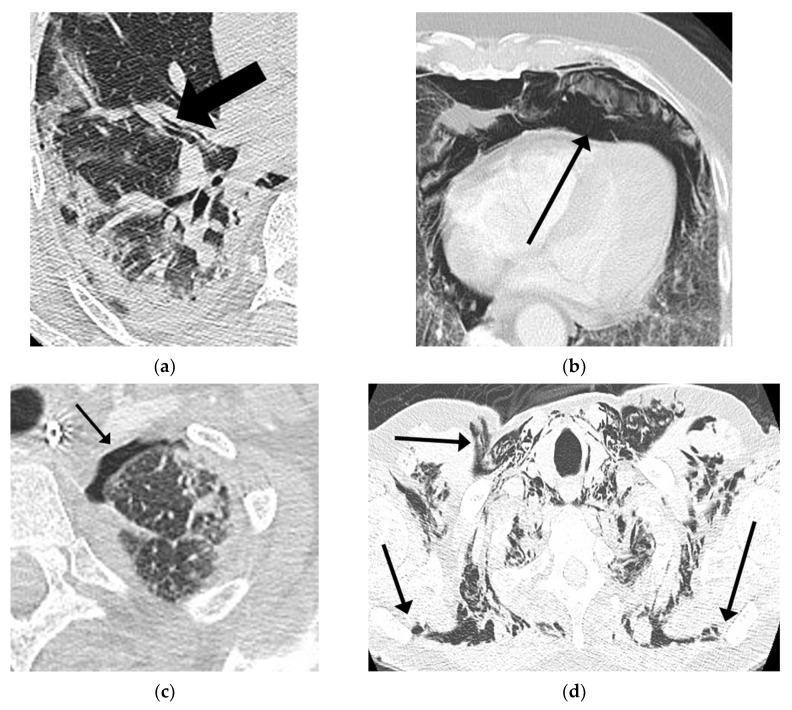

(1) Background: COVID-19 is a novel cause of acute respiratory distress syndrome (ARDS). Indeed, with the increase of ARDS cases due to the COVID-19 pandemic, there has also been an increase in the incidence of cases with pneumothorax (PNX) and pneumomediastinum (PNM). However, the incidence and the predictors of PNX/PMN in these patients are currently unclear and even conflicting. (2) Methods: The present observational study analyzed the incidence of barotrauma (PNX/PNM) in COVID-19 patients with moderate-severe ARDS hospitalized in a year of the pandemic, also focusing on the three waves occurring during the year, and treated with positive-pressure ventilation (PPV). We collected demographic and clinical data. (3) Results: During this period, 40 patients developed PNX/PNM. The overall incidence of barotrauma in all COVID-19 patients hospitalized in a year was 1.6%, and in those with moderate-severe ARDS in PPV was 7.2% and 3.8 events per 1000 positive-pressure ventilator days. The incidence of barotrauma in moderate-severe ARDS COVID-19 patients during the three waves was 7.8%, 7.4%, and 8.7%, respectively. Treatment with noninvasive respiratory support alone was associated with an incidence of barotrauma of 9.1% and 2.6 events per 1000 noninvasive ventilator days, of which 95% were admitted to the ICU after the event, due to a worsening of respiratory parameters. The incidence of barotrauma of ICU COVID-19 patients in invasive ventilation over a year was 5.8% and 2.7 events per 1000 invasive ventilator days. There was no significant difference in demographics and clinical features between the barotrauma and non-barotrauma group. The mortality was higher in the barotrauma group (17 patients died, 47.2%) than in the non-barotrauma group (170 patients died, 37%), although this difference was not statistically significant ( = 0.429). (4) Conclusions: The incidence of PNX/PNM in moderate-severe ARDS COVID-19 patients did not differ significantly between the three waves over a year, and does not appear to be very different from that in ARDS patients in the pre-COVID era. The barotrauma does not appear to significantly increase mortality in COVID-19 patients with moderate-severe ARDS if protective ventilation strategies are applied. Attention should be paid to the risk of barotrauma in COVID-19 patients in noninvasive ventilation because the event increases the probability of admission to the intensive care unit (ICU) and intubation.

(1) 背景:新型冠状病毒肺炎(COVID-19)是急性呼吸窘迫综合征(ARDS)的一种新病因。事实上,随着COVID-19大流行导致ARDS病例增加,气胸(PNX)和纵隔气肿(PNM)病例的发生率也有所上升。然而,这些患者中PNX/PMN的发生率及预测因素目前尚不清楚,甚至存在相互矛盾的情况。(2) 方法:本观察性研究分析了在大流行的某一年中住院的中度至重度ARDS的COVID-19患者气压伤(PNX/PNM)的发生率,同时关注该年发生的三波疫情期间的情况,并对接受正压通气(PPV)治疗的患者进行研究。我们收集了人口统计学和临床数据。(3) 结果:在此期间,40例患者发生了PNX/PNM。该年所有住院的COVID-19患者中气压伤的总体发生率为1.6%,接受PPV治疗的中度至重度ARDS患者中气压伤的发生率为7.2%,每1000个正压通气日发生3.8次。中度至重度ARDS的COVID-19患者在三波疫情期间气压伤的发生率分别为7.8%、7.4%和8.7%。仅采用无创呼吸支持治疗时,气压伤的发生率为9.1%,每1000个无创通气日发生2.6次,其中95%的患者在事件发生后因呼吸参数恶化而入住重症监护病房(ICU)。一年中接受有创通气的ICU COVID-19患者气压伤的发生率为5.8%,每1000个有创通气日发生2.7次。气压伤组与非气压伤组在人口统计学和临床特征方面无显著差异。气压伤组的死亡率(17例死亡,47.2%)高于非气压伤组(170例死亡,37%),尽管这种差异无统计学意义(P = 0.429)。(④) 结论:中度至重度ARDS的COVID-19患者中PNX/PNM的发生率在一年中的三波疫情期间无显著差异,且似乎与COVID-19大流行前时代ARDS患者的发生率没有很大不同。如果采用保护性通气策略,气压伤似乎不会显著增加中度至重度ARDS的COVID-19患者的死亡率。应关注COVID-19患者无创通气时的气压伤风险,因为该事件会增加入住重症监护病房和插管的可能性。